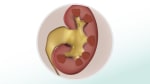

Un cálculo renal comienza como un fragmento diminuto de cristal en el riñón. Cuando la orina sale del riñón es posible que saque el cristal consigo, o el cristal podría permanecer en el riñón. Si el cristal permanece en el riñón, con el tiempo, más cristales pequeños se le adhieren y forman un cálculo renal más grande.

La mayoría de los cálculos salen del riñón y se desplazan por las vías urinarias cuando aún son lo suficientemente pequeños como para que puedan eliminarse del cuerpo con facilidad. No es necesario ningún tratamiento para estos cálculos.

Los cálculos más grandes podrían atascarse en los conductos que transportan la orina desde el riñón hasta la vejiga (uréteres). Esto puede causar dolor y posiblemente obstruir el flujo de la orina hacia la vejiga y fuera del cuerpo. El dolor a menudo empeora en el transcurso de 15 a 60 minutos hasta que se vuelve grave. El dolor puede aliviarse cuando el cálculo deja de obstruir el flujo de la orina y, a menudo, desaparece cuando el cálculo entra en la vejiga. A menudo, es necesario recibir tratamiento médico para los cálculos más grandes.